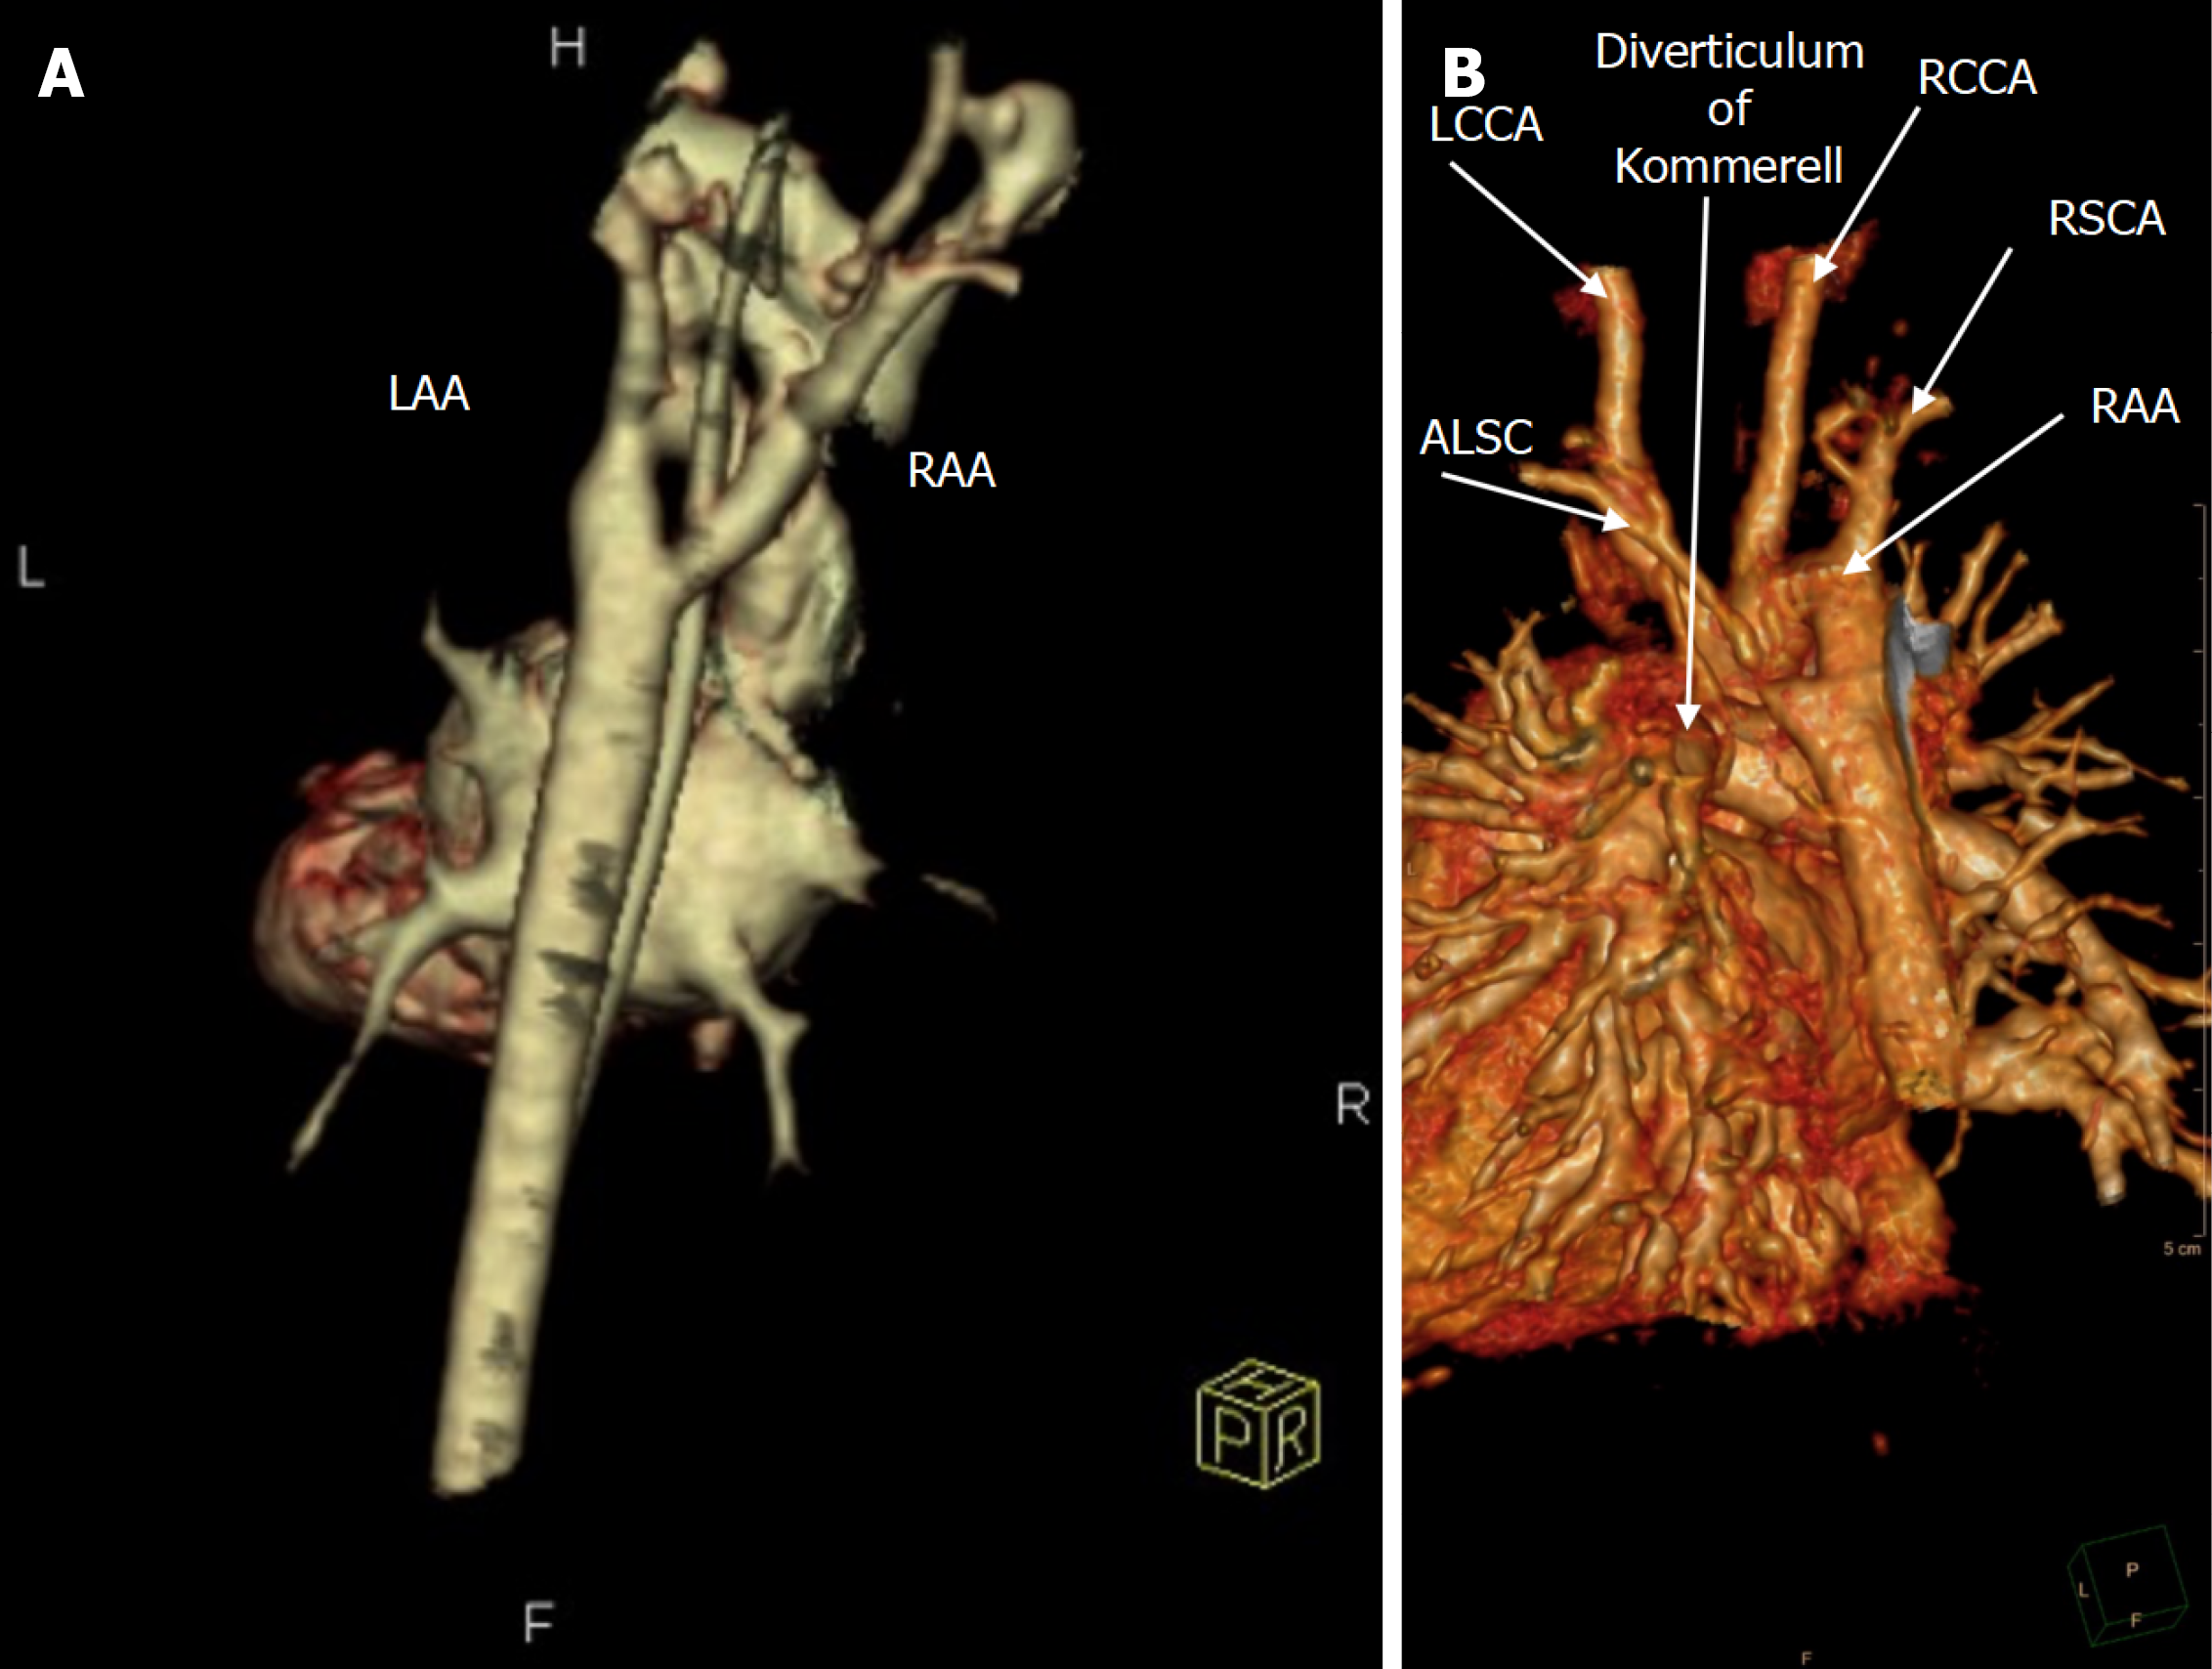

Figure 1 illustrates the echocardiographic findings of a 38-month-old patient with DAA, and Figure 2A shows the corresponding chest radiograph. Notably, this patient had previously been diagnosed with asthma and experienced recurrent respiratory infections requiring multiple antibiotic courses and repeated hospitalizations prior to definitive diagnosis.

All patients underwent preoperative TTE and CTA for anatomical delineation (Figures 3 and 4). One patient additionally underwent diagnostic cardiac catheterization (Figure 2B).